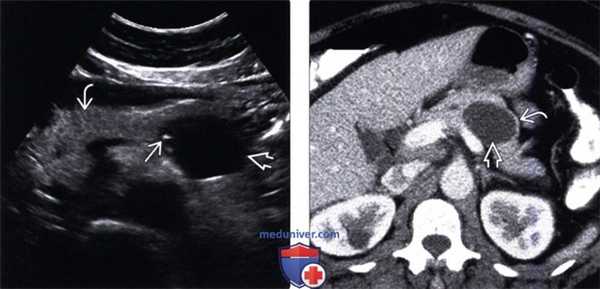

(Слева) На аксиальной КТ с контрастным усилением у женщины 38 лет определяется большое кистозное образование сложной структуры, с множественными перегородками и узлом в стенке, накапливающим контраст. Образование исходит из хвоста поджелудочной железы, обладает экзофитным ростом, распространяясь в каудальном направлении.

(Справа) На корональной КТ с контрастным усилением у этой же пациентки определяется объемное образование большого размера с множественными перегородками и узлом в стенке, накапливающим контраст. Было выполнено оперативное вмешательство, при исследовании резектата подтвердилась муцинозная кистозная опухоль высокой степени дисплазии. (Слева) На аксиальной КТ с контрастным усилением у женщины 34 лет визуализируется простая однокамерная киста в хвосте поджелудочной железы. Было выполнено оперативное вмешательство, подтвердилась муцинозная кистозная опухоль низкой степени дисплазии. Стенка не утолщена, узлы в стенке отсутствуют, что не позволяет заподозрить злокачественную опухоль.

(Справа) На аксиальной КТ с контрастным усилением визуализируется большое кистозное образование в теле поджелудочной железы, разделенное перегородками на крупные камеры. Обратите также внимание на периферическое обызвествление и мягкотканный узел в стенке. Эти изменения являются классическими признаками муцинозной кистозной опухоли. (Слева) На аксиальной КТ с контрастным усилением у женщины 61 года определяется кистозное образование в хвосте поджелудочной железы с грубыми обызвествлениями в стенке.

4. УЗИ признаки муцинозной кистозной опухоли поджелудочной железы:

• Серошкальное исследование:

о Многокамерное кистозное образование с эхогенными перегородками:

- Часто в сочетании с утолщением стенки, возможно, с наличием узлов

о Может также выглядеть как однокамерное анэхогенное образование